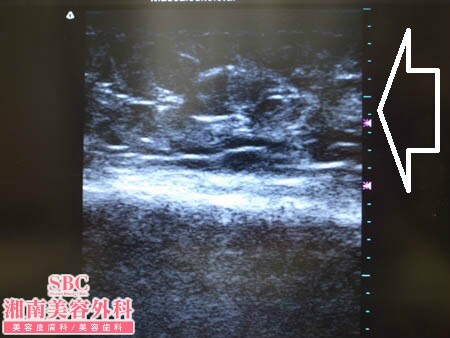

No.126715【脂肪吸引】日本人初!ライポマティック認定医であるあの有名な根こそぎ竹田先生の劇的ビフォーアフター!〜ニューヨーク在住の患者様のスネ周囲の皮下脂肪を根こそぐ!左スネ周囲・術中3Dタッチビューその1〜